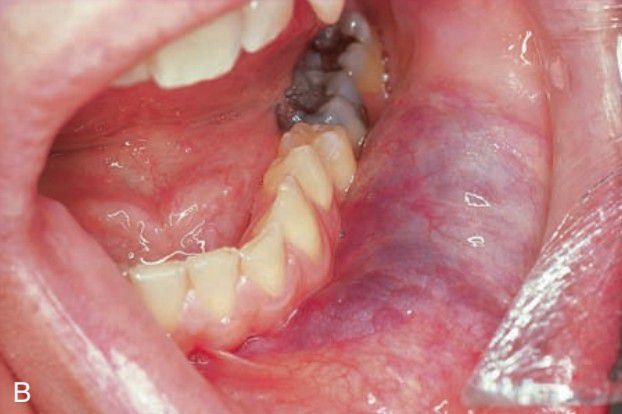

Vascular malformation

Congenital vascular malformations are generally persistent lesions that grow with the individual and do not involute. They may represent arteriovenous shunts and exhibit a bruit or thrill on auscultation.